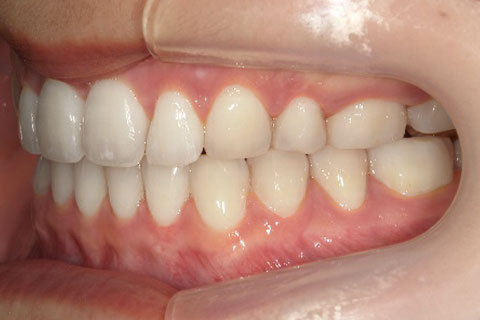

主訴:上下の歯並びのガタガタが気になる

診断名:上下顎叢生

症状:上下顎叢生

患者プロフィール:北九州市・小倉北区30代女性

治療方針:非抜歯治療

治療装置:マウスピース型矯正治療(インビザライン)

抜歯:無し

治療期間:一年半

通院回数:30回

リテーナー:上顎プレートタイプリテーナー 下顎フィクスタイプリテーナー

治療費用:検査診断料(20,000)+装置料金(500,000)+管理調整料(150,000) +装置撤去時診断料(10,000) +保定装置料金(20,000)=700,000(消費税込)

リスク副作用:痛み・治療後の後戻り・歯根吸収・歯髄壊死

詳しい症例説明:この患者さんはガタガタが気になり来院されました。マウスピースタイプの矯正装置で比較的短期間で治療を終えることができました。インビザライン(マウスピース矯正治療)で矯正治療を行うことで取り外して食事ができ、痛みもそれほど感じなかったとのことです。